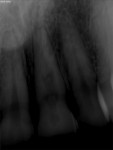

A 25-year-old Caucasian female patient with an unremarkable medical history noticed when reviewing photographs that her left maxillary central incisor was discolored (Figure 1). Prior to this, the patient had not noticed the discoloration. Her dental history revealed past orthodontic treatment and possible trauma due to a tubing accident.

The initial clinical examination showed an intact crown with no caries or restorations present and a vital pulp. However, periapical radiographs revealed a well-defined symmetrical radiolucency, which ballooned out of the pulp chamber (Figure 2). No periapical lesion or widening of the periodontal ligament space was found. The patient had an endodontic consultation, which included an intraoral examination, shifted periapical radiographs, and a CBCT image (Figure 3), to assess the presence and type of resorption. CBCT imaging is crucial in differentiating between internal and external resorption and determining the extent of the lesion, which will affect the treatment plan and outcome.1,5